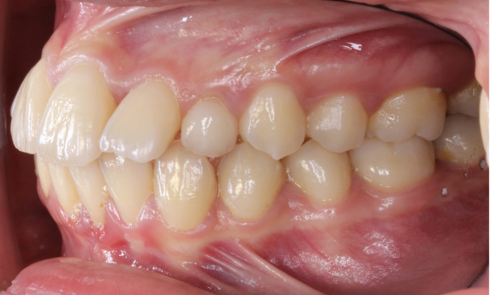

Grand Prix l’orthodontiste – Orthoplus Premier lauréat ex aequo Catégorie adultes Guillaume Lecocq Spécialiste qualifié en orthopédie dento-faciale, Valenciennes Diagnostic...